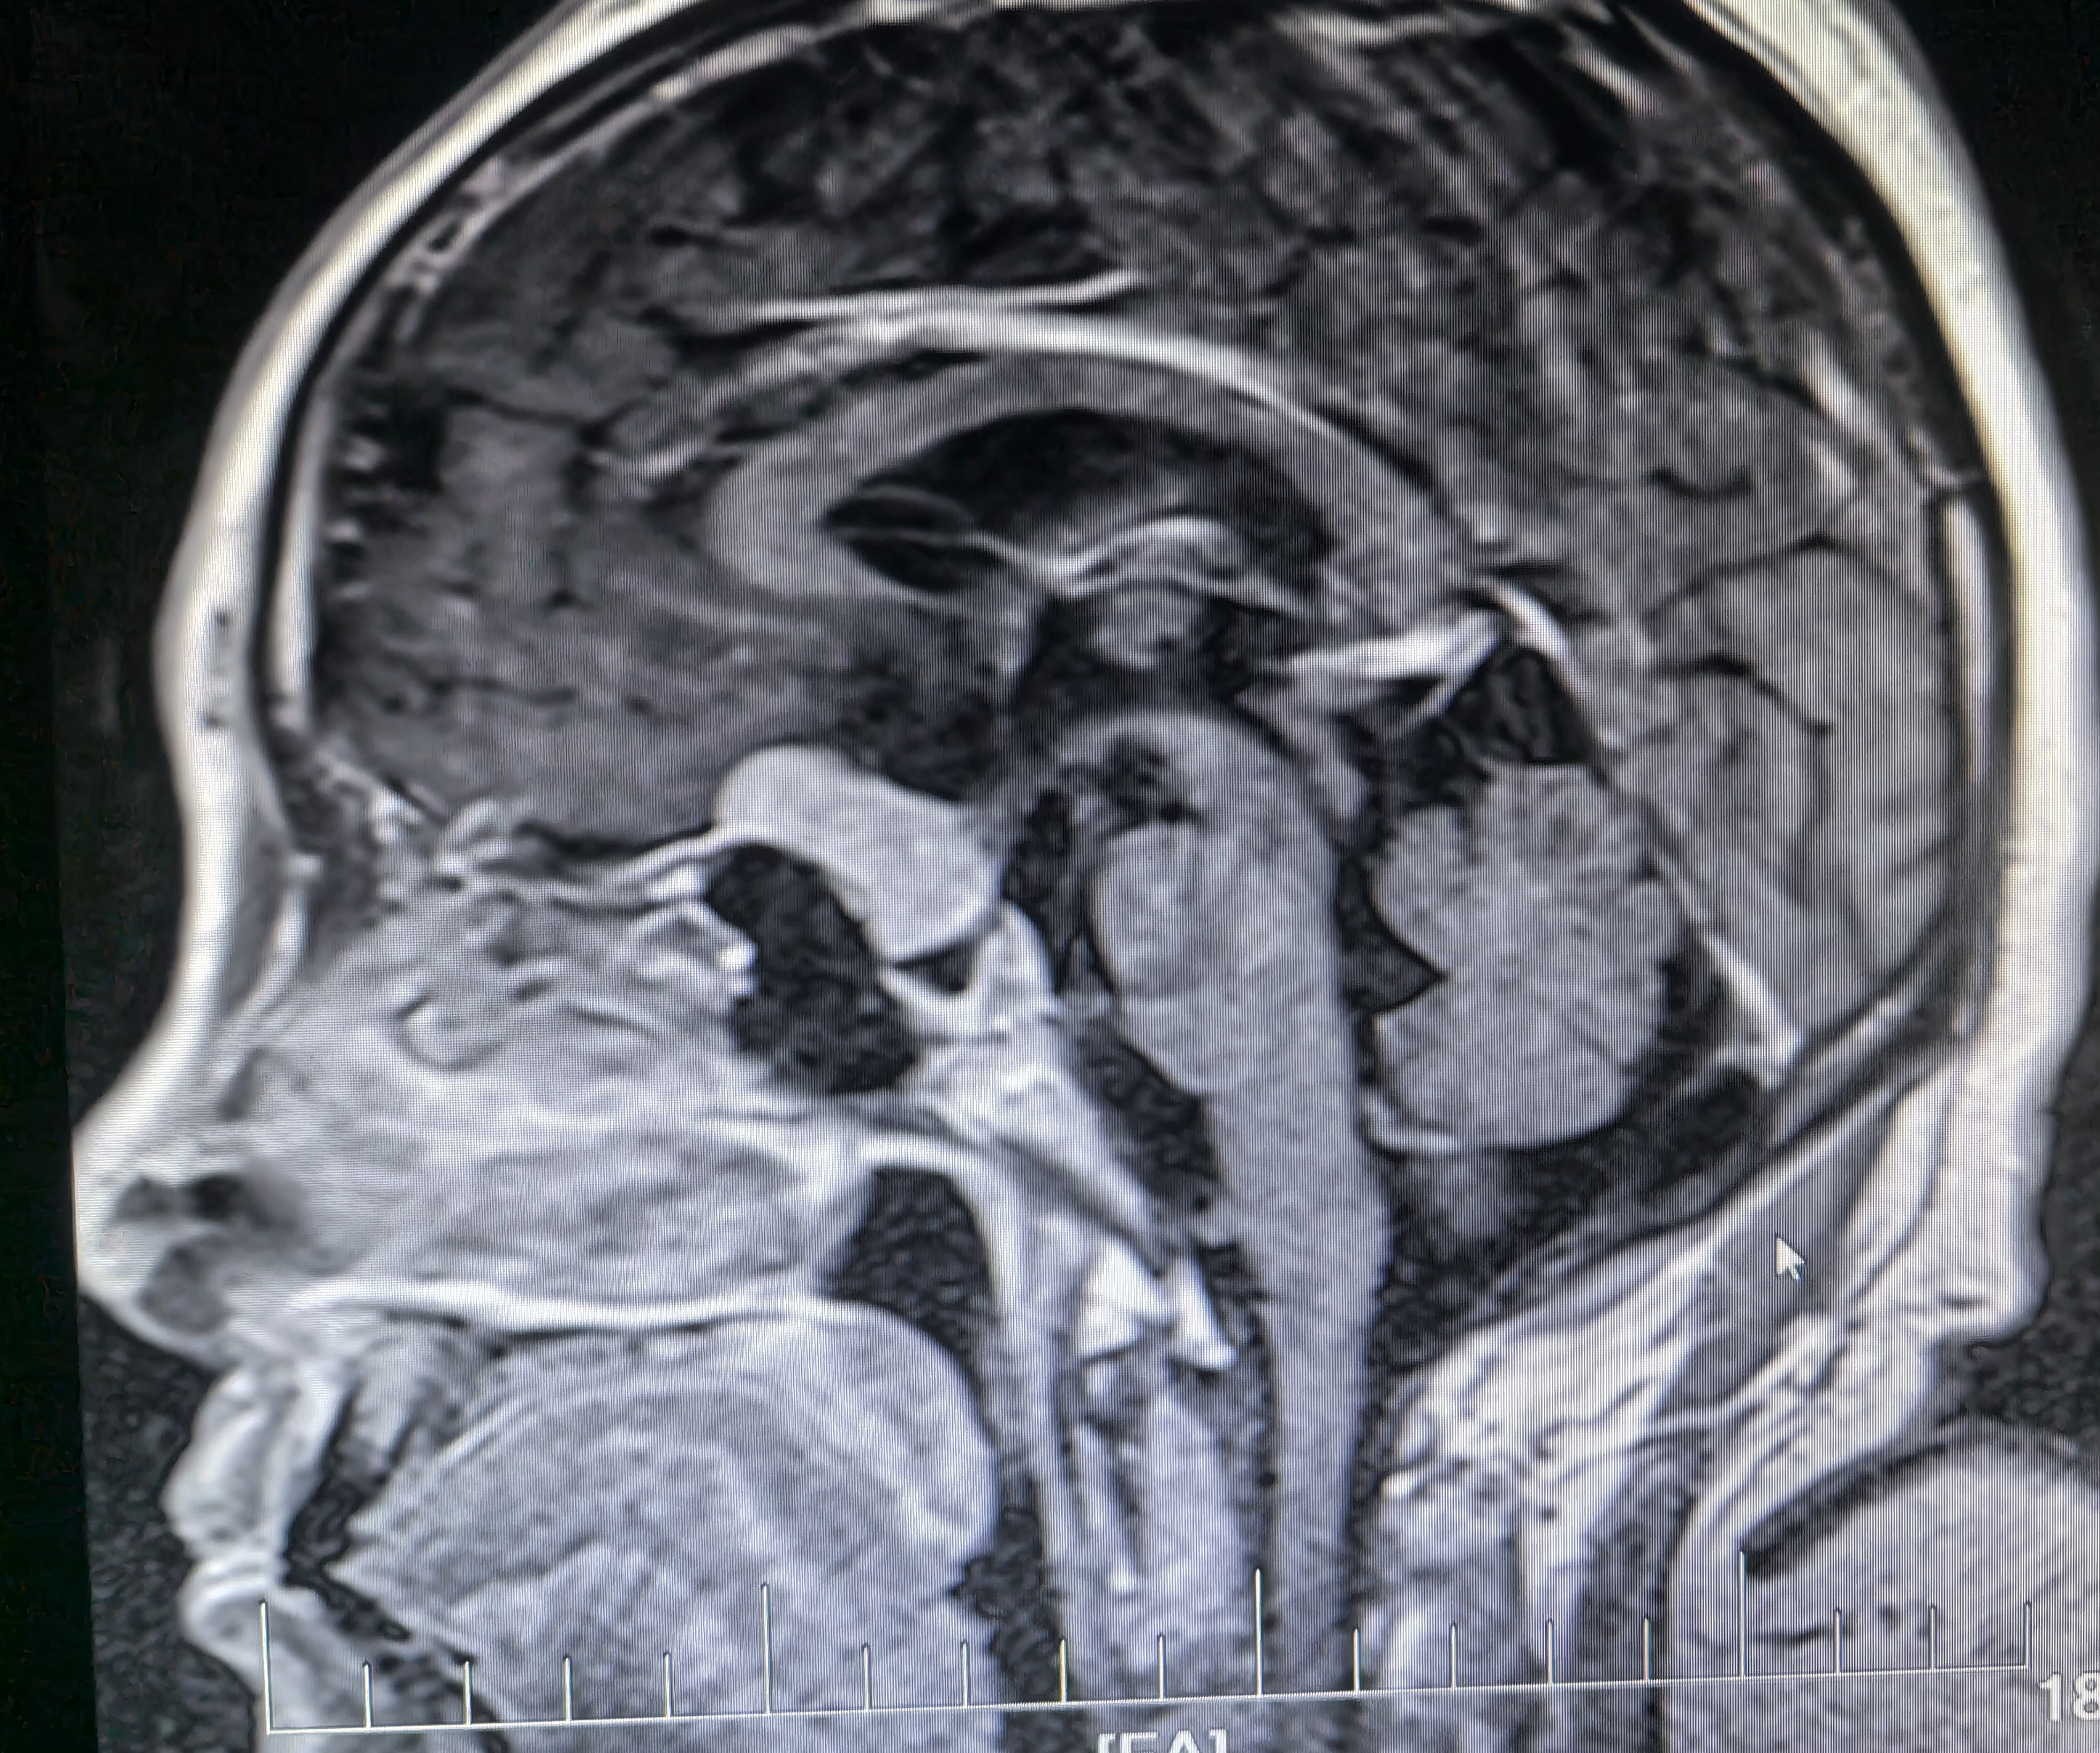

下面展示本病房几例病例:

病例三